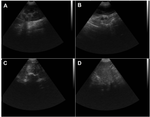

Las imágenes radiológicas sirvieron para evaluar la extensión local y regional de la enfermedad, ayudando a identificar evidencias de metástasis. La radiografía torácica (ver figura 1A) permitió evaluar la integridad de los pulmones, no mostró evidencia de nódulos pulmonares múltiples, adenomegalia mediastínica o derrame pleural, que forman el patrón metastásico. De manera similar, la radiografía abdominal (ver figura 1B) permitió asegurar que no existía metástasis hepáticas/esplénicas o invasión local, al mostrar al espécimen canino sin hepatomegalia y esplenomegalia, presencia de masas abdominales o calcificaciones. La toma de imágenes radiográficas de la región mamaria no se consideró necesaria debido a las limitaciones de la técnica para distinguir la naturaleza y condición de las lesiones neoplásicas.

Figura 1. Imágenes radiológicas de un canino hembra Husky Siberiano de 10 años de edad. (A) Radiografía torácica con proyección ventrodorsal, (B) Radiografía abdominal con proyección lateral.

La figura 2 correspondiente a las imágenes del examen ecográfico abdominal que muestra al explorar la glándula mamaria lesiones compatibles con carcinoma sin evidencia de condición metastásica. Se reporta la presencia de masas heterogéneas de estructura irregular con áreas hipoecoicas e hiperecoicas con bordes mal definidos, vascularización aumentada, microcalcificaciones y áreas anecoicas dentro del tumor debido a degradación tisular. No se observa invasión local con extensión a tejidos adyacentes o alteración de los ganglios linfáticos regionales.

Figura 2. Imágenes de ecografía abdominal de un canino hembra Husky Siberiano de 10 años de edad. (A) Riñón izquierdo, (B) glándula mamaria, (C) glándula mamaria, (D) bazo.